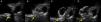

A 61-year-old man, with a history of coronary heart disease and percutaneous coronary intervention, with stents in the right coronary and circumflex arteries, was referred to our center for left atrial appendage (LAA) closure. He had atrial fibrillation with high thromboembolic risk (CHA2DS2VASc=4) and oral anticoagulation was formally contraindicated because of recurrent severe bleeding. Selective angiography of the LAA (Video 1) showed a close relationship between the LAA (Figure 1, asterisk) and the circumflex artery (Figure 1, arrow), well defined by the previously implanted stents. A computed tomography scan performed after a previous episode of diffuse alveolar hemorrhage showed similar findings (Figure 2, arrow). A 22-mm Amplatzer Amulet device was successfully placed, with no residual leak. Intraoperative monitoring by transesophageal echocardiography and post-procedural radioscopy confirmed the close relationship between the device and the circumflex artery (Figures 3 and 4, Videos 2 and 3), which is vital to keep in mind in order to prevent complications during the procedure.

After the Amplatzer was completely deployed, radioscopy confirmed the relationship between the distal lobe of the device and the coronary artery. Although in this patient this latter structure was easily delineated by the previously implanted stents, it is vital to consider this anatomical relationship during the occlusion procedure.

LAA closure is a safe and effective intervention used to prevent stroke and systemic embolism in patients with atrial fibrillation and contraindications for oral anticoagulation. Nevertheless, there may be procedure-related complications such as device embolization and left atrial wall perforation. The close relationship between the LAA and circumflex artery place this latter structure and its branches (including the sinus node artery in 30% of patients) at risk during the procedure. This condition must be considered if the patient develops atrial arrhythmias or signs of myocardial ischemia during the procedure.